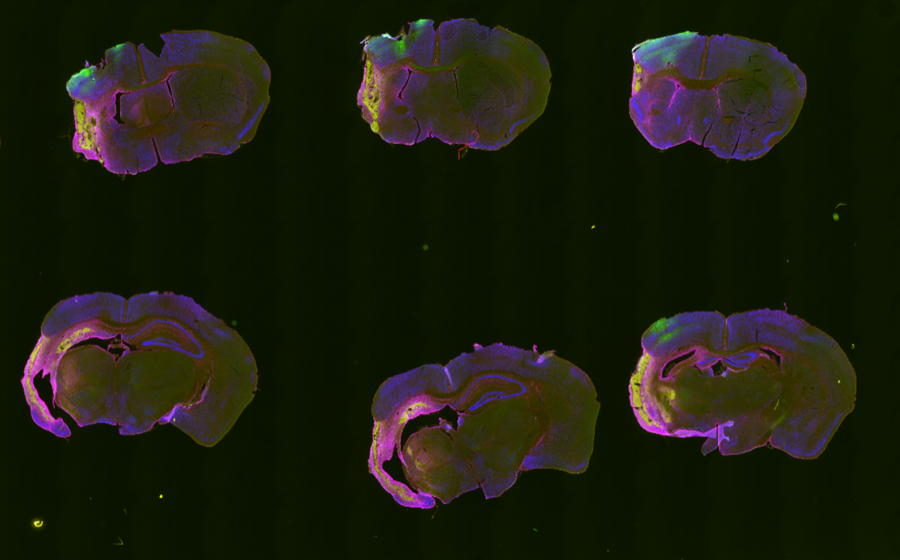

Outputs

Analysis outputs include segmented infarct masks, merged review images, and CSV summaries saved per animal for quantitative comparison.